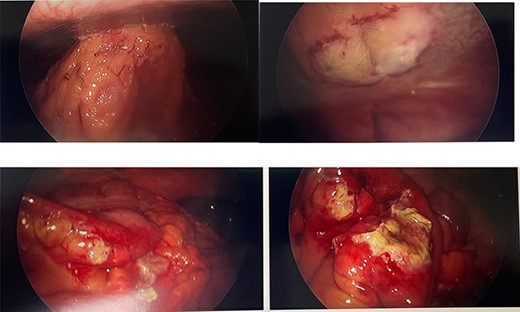

He presented to the emergency room with worsening lower abdominal pain for 1 week after undergoing bilateral ilioinguinal and iliohypogastric hot RF ablation with Pain Management. Per outside hospital, he underwent RF ablation at 80°Cfor 90 s. Computed tomography imaging was obtained which showed an inflamed area of small bowel with a localized area of pneumoperitoneum (Fig. 1). Given his normal vitals, lack of peritoneal findings on abdominal exam, and leukocytosis 14 000 with otherwise unremarkable lab work, we elected to initially treat with IV antibiotics, bowel rest and serial abdominal exams. On hospital Day 3, he was taken to the operating room for persistent pain and failure to improve. A diagnostic laparoscopy was performed. There was a scarred area on the peritoneum with adherent small bowel and omentum found. This single adhesion was taken down and the involved jejunal segment was inspected revealing a full-thickness perforation with surrounding erythematous bowel (Fig. 2). The intraoperative findings and timing post-RF ablation were consistent with delayed perforation secondary to jejunal thermal injury. A laparoscopic small bowel resection with intracorporeal stapled anastomosis was performed. His postoperative course was uneventful, and he was ultimately discharged post-op Day 3 after tolerating a diet and having bowel function.

Intraoperative photos. Top right: omentum and small bowel adhered to anterior abdominal wall. Top left: scarred peritoneum after removing adhesion, lateral to medial umbilical ligament. Bottom: small bowel with isolated full-thickness necrosis and perforation and surrounding erythema from thermal injury.